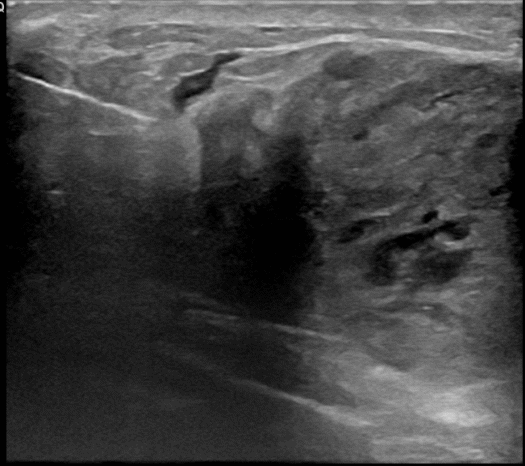

아산유외과 개원후 767번째 유방암진단

상기환자 만져지는 멍울로 내원하신 30대 후반 여성분으로 우측 조직검사 시행해 침윤성 유방암으로 진단되었습니다